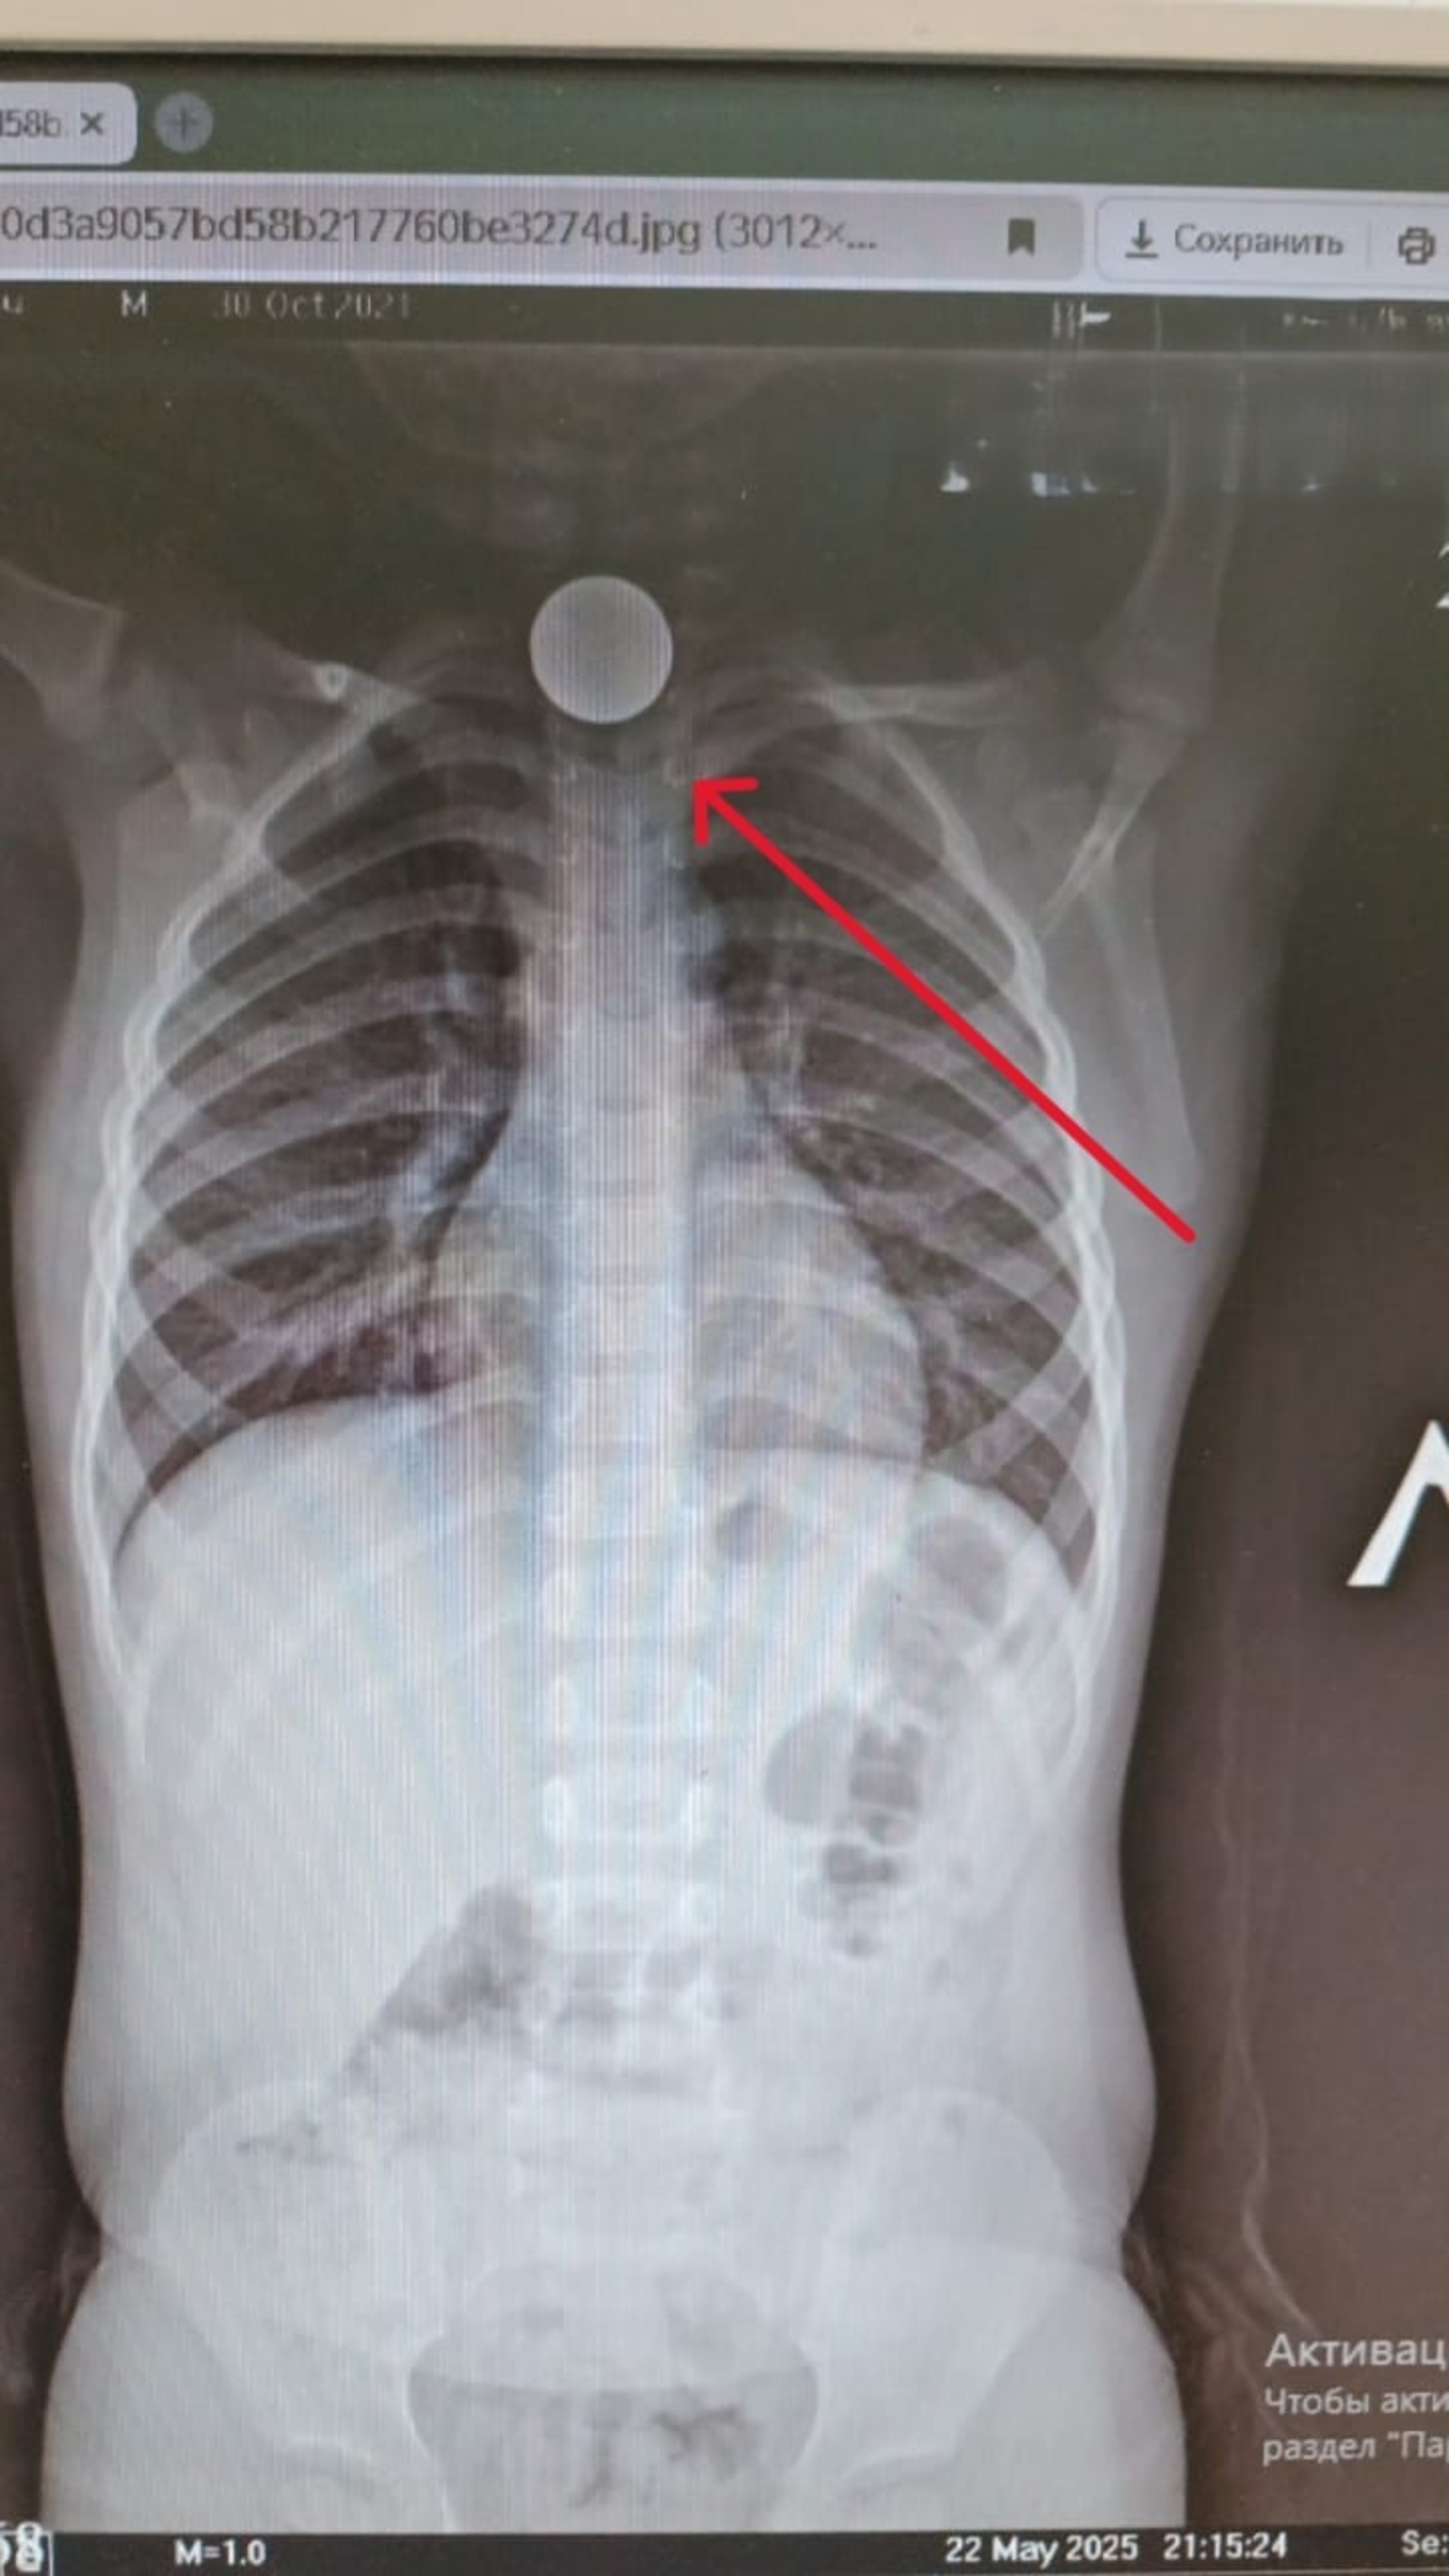

Ребенок проглотил камушек

Ребенок проглотил камушек 108 фото